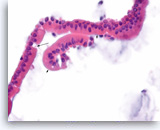

Benign duodenal epithelial cells,

Pancreas FNA, ThinPrep.

Normal duodenal epithelial cells form large cohesive clusters with prominent papillary projections. Within the projections, there are scattered cells with large intracytoplasmic vacuoles and eccentrically located nuclei, which represent goblet cells. Fragments of benign duodenal epithelium can be seen as contaminants during trans-duodenal FNA of pancreatic lesions. (Courtesy of Dr. Andrew Fischer)

40X

Benign duodenal epithelial cells,

Pancreas FNA, ThinPrep.

Normal duodenal epithelial cells form large cohesive clusters with prominent papillary projections. Within the projections, there are scattered cells with large intracytoplasmic vacuoles and eccentrically located nuclei, which represent goblet cells. Fragments of benign duodenal epithelium can be seen as contaminants during trans-duodenal FNA of pancreatic lesions. (Courtesy of Dr. Andrew Fischer)

40X